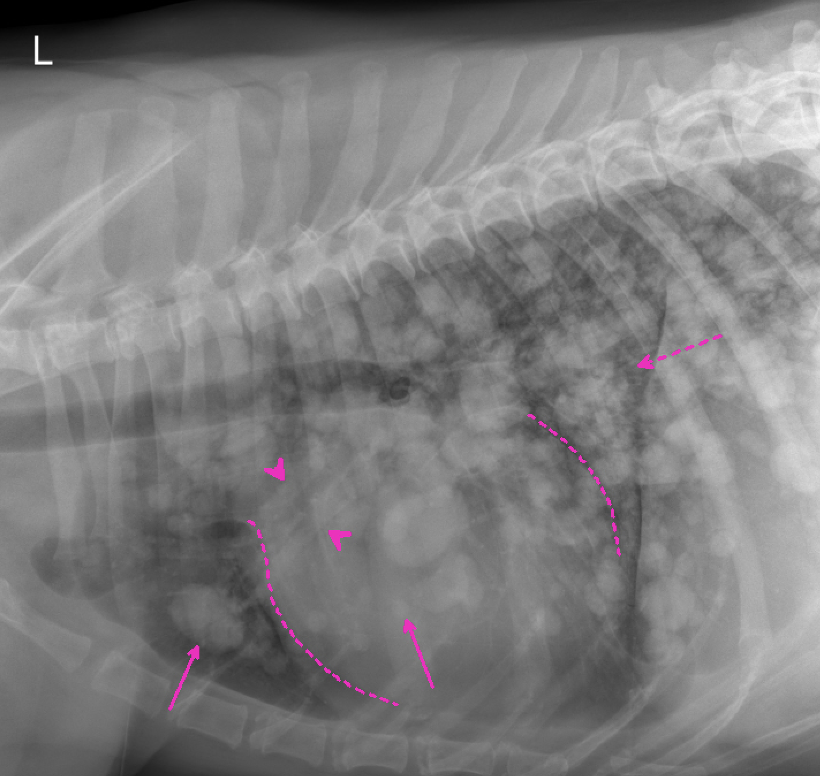

Vielen Dank für die Zusendung der Röntgenbilder. Ein wirklich eindrucksvoller Fall! Es liegen zwei Röntgenaufnahmen des linken Humerus, inkl. Ellbogengelenk, im medio-lateralen, sowie kaudo-kranialem Strahlengang vor. Begleitend besteht eine Röntgenaufnahme des Thorax in dextro-sinistralem Strahlengang (Abb. 1, Abb. 2). Im Röntgenbild der linken Vordergliedmaße zeigt sich im Bereich der gesamten Diaphyse des Humerus, bis in die angrenzenden metaphysären Abschnitte reichend, eine hochgradige, unregelmäßige osteoproliferative Reaktion (blaue Pfeile Abb. 3). Diese periostale Reaktion weist eine heterogene Röntgendichte auf. An ihrer ausgeprägtesten Stelle übersteigt die Proliferation den Durchmesser des normalen Humerus deutlich. Besonders an der kaudalen Humeruskontur besteht hochgradige, laminar geschichtete Knochenneubildung (gelbe Pfeile, Bild links).

Im Thoraxröntgen zeigen sich in allen Lungenlappen multifokale, noduläre Weichteilverschattungen unterschiedlicher Größe, wobei die größte eine Länge von 3,8cm und eine Breite von 2,6cm aufweist (exemplarisch pinke Pfeile). Generalisiert besteht zudem vor allem in den kaudalen Lungenlappen geringgradige (pink gestrichelter Pfeil), sowie im akzessorischen Lungenlappen moderate unstrukturierte Lungenzeichnung. Die Herzsilhouhette ist generalisiert globoid vergrößert (pink gestrichelte Linien). Die kranialen Lungengefäße wirken prominent, sind jedoch kleiner als die proximale Breite im Bereich der vierten Rippe (pinke Pfeilköpfe). Mediastinale Strukturen, Pleuralraum, Trachea, Ösophagus, sowie sichtbare ossäre Anteile stellen sich ohne besonderen Befund dar.